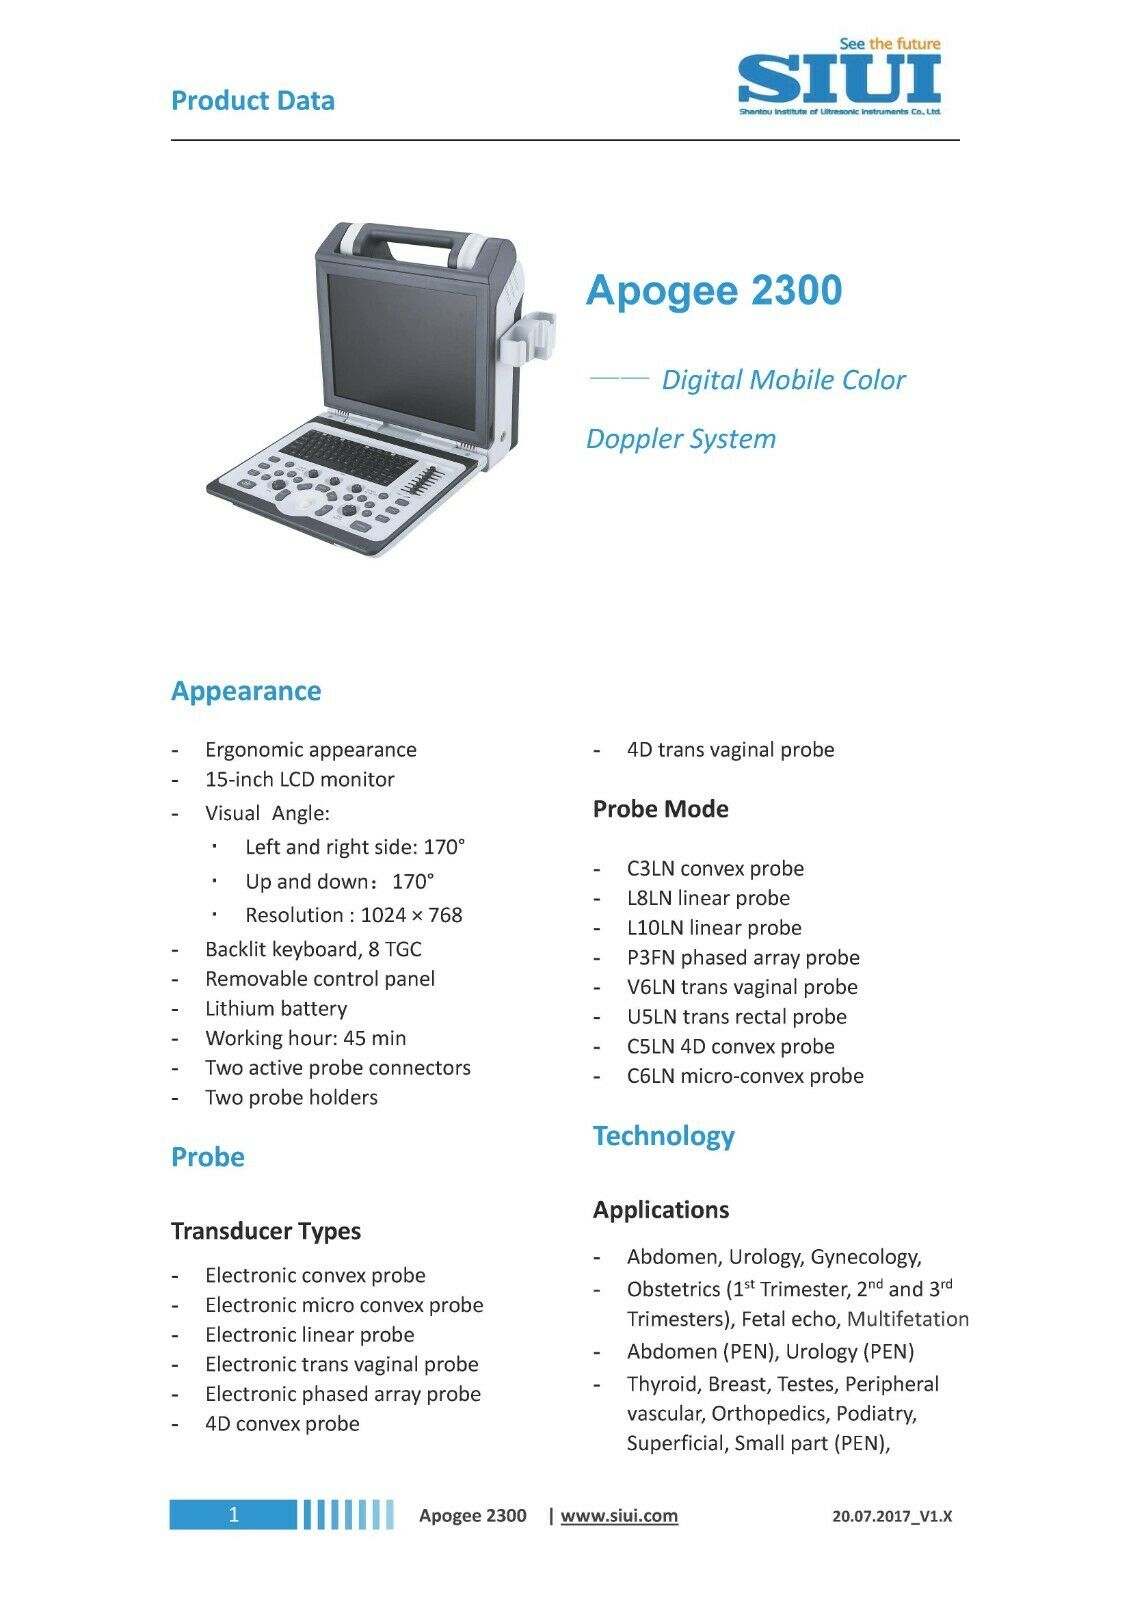

The Portable OB/GYN Ultrasound Machine, specifically the SIUI Apogee 2300, represents a breakthrough in medical imaging technology. Designed with convenience in mind and equipped with advanced features, this ultrasound machine is an excellent choice for obstetrics and gynecology practitioners who need reliable, high-quality imaging on the go.

This state-of-the-art machine comes with two probes, ensuring versatility for different diagnostic needs. The SIUI Apogee 2300 supports DICOM (Digital Imaging and Communications in Medicine) which allows seamless integration with hospital information systems and ensures efficient workflow and storage management. The portability of this machine does not compromise its performance, as it delivers crystal-clear images that are critical for precise diagnostics.

One of the most significant benefits of the Portable OB/GYN Ultrasound Machine is its ease of use. The SIUI Apogee 2300 features an intuitive interface and ergonomic design, making it user-friendly for healthcare providers. This means less time spent on training and more time dedicated to patient care. Furthermore, the compact design and lightweight nature of the machine make it easy to transport between examination rooms and even to different clinical settings or remote locations, ensuring that high-quality care is always within reach.

Another key advantage is the high resolution imaging capabilities. The portable OB/GYN ultrasound machine, with its advanced image processing software, delivers detailed images that can be crucial for diagnosing various conditions. From routine prenatal scans to complex gynecological assessments, the SIUI Apogee 2300 stands out in its ability to provide accurate and reliable results.

Moreover, the machine's durability ensures that it can withstand the rigors of frequent use. Its robust build and quality components mean that it will continue to function optimally even in demanding environments. This longevity not only represents a good investment for clinics and healthcare facilities but also ensures consistent diagnostic performance over time.

In addition to its technical features, the Portable OB/GYN Ultrasound Machine is also designed with patient comfort in mind. The smooth operation and efficient scanning reduce the need for lengthy or repeated procedures, minimizing discomfort and improving patient experience. The two included probes offer flexibility in imaging, allowing for both abdominal and transvaginal examinations with ease.

Finally, the SIUI Apogee 2300 isn't just about convenience and quality imaging; it also represents a cost-effective solution. Its competitive pricing and long-term durability offer excellent value for money, making it an attractive option for clinics and medical practices looking to enhance their diagnostic capabilities without breaking the bank.

In summary, the Portable OB/GYN Ultrasound Machine SIUI Apogee 2300 with 2 Probes and DICOM support is a powerful, versatile, and efficient tool for modern obstetrics and gynecology practices. It provides high-quality imaging, user-friendly operation, and robust durability, all while ensuring patient comfort and efficient data management. Whether for routine check-ups or complex diagnostic procedures, this ultrasound machine is an invaluable addition to any healthcare setting, offering both clinicians and patients numerous benefits.